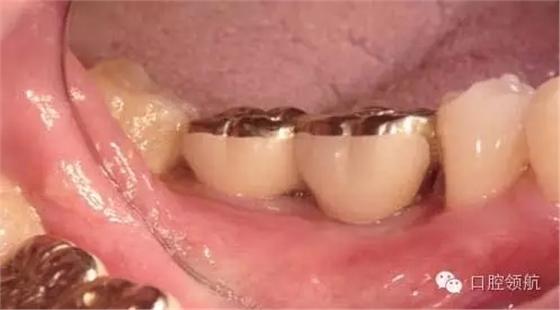

1周后(左下第六顆牙) 的牙動度值是:+2∕+2; 7 :-2∕-2,6周后(左下第六顆牙) 的牙動度值是:-1∕0; 7 :-3∕-3,然后安裝調(diào)改后的上部修復(fù)體(圖5、圖6)。

圖6 最終上部結(jié)構(gòu)安裝后6個月的口內(nèi)像。